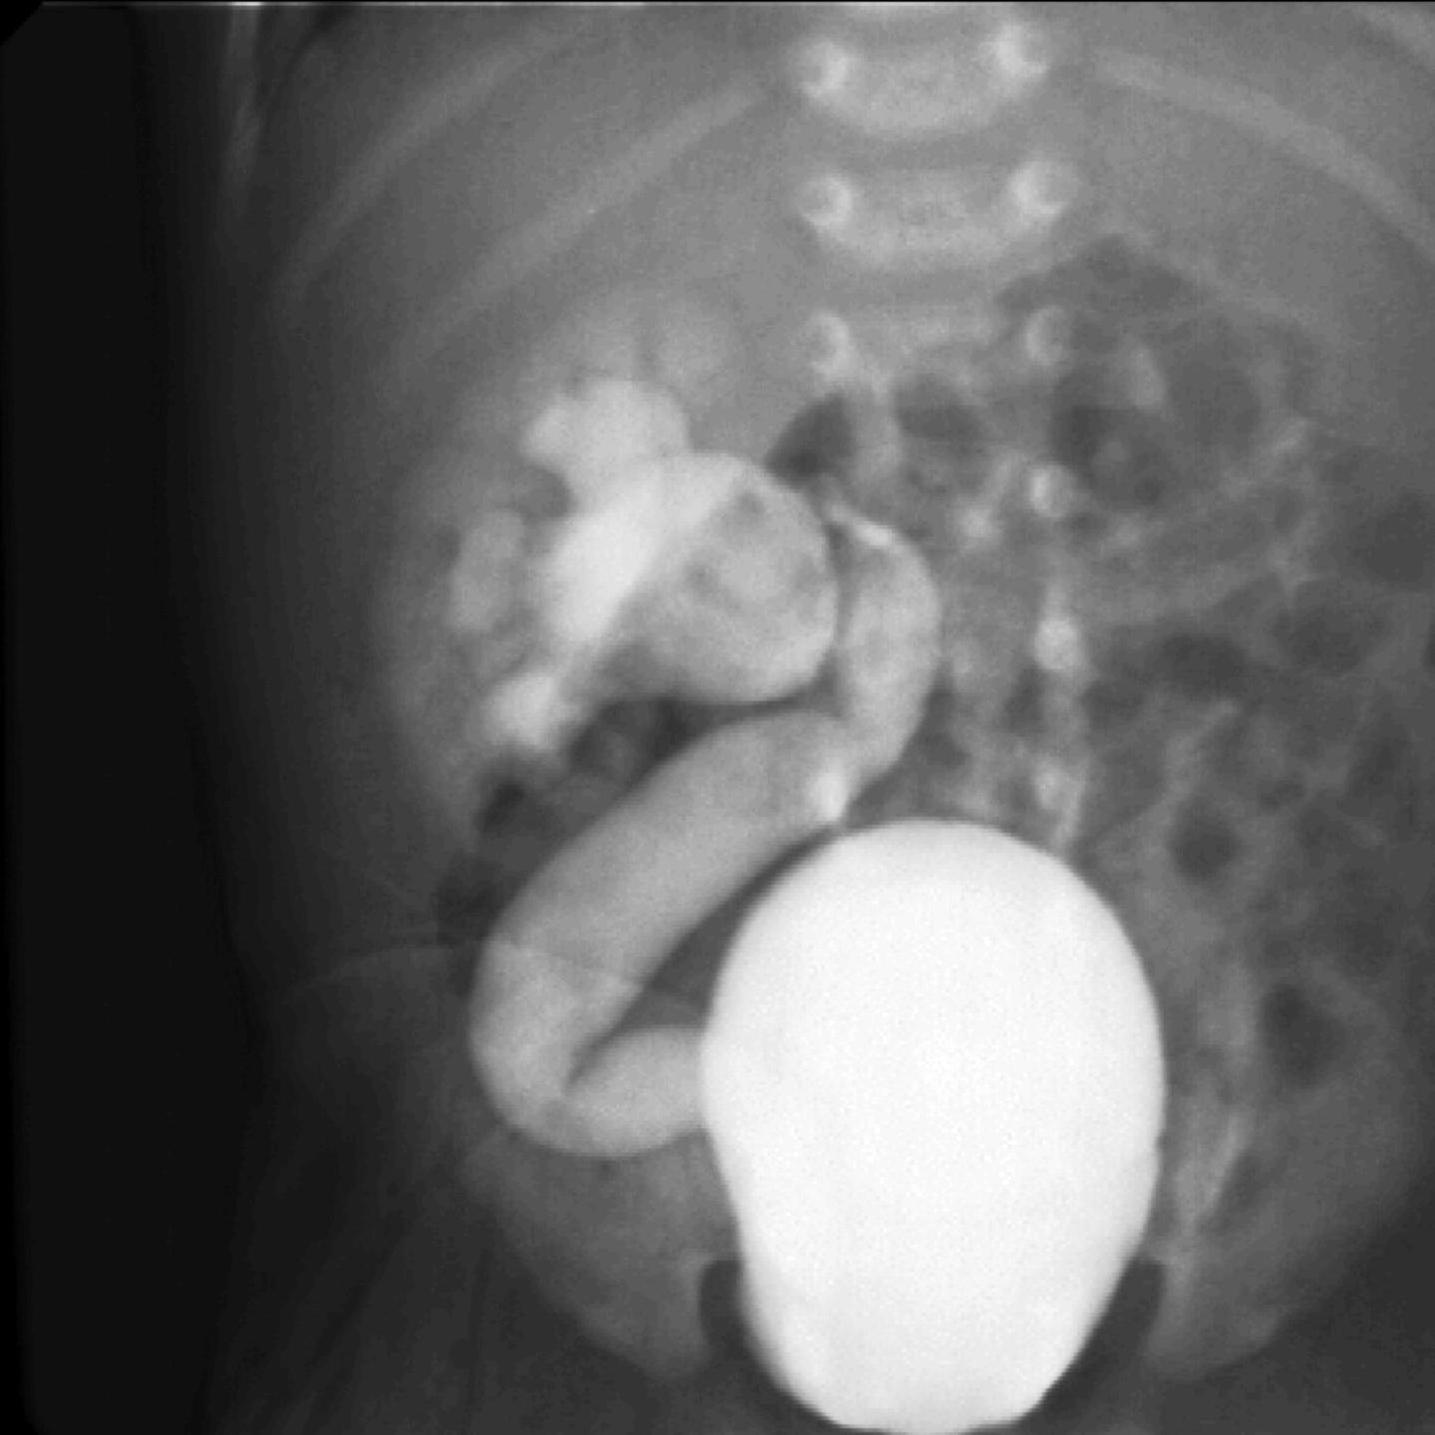

Invagination. A distal intestinal loop invaginating to a proximal intestinal loop can result in a mechanical intestinal obstruction, and cause ischemic damage. It most frequently occurs in infants (3-24 months) with recurring, colic-like complaints, distended intestines, a palpable mass and with frequent vomiting and bloody stool. Invagination requires immediate diagnosis and desinvagination. US exam reveals the invaginated intestines as a “target” sign in axial cross section and looks like a “pseudokidney” in longitudinal cross section. The therapy is hydrostatic or pneumatic desinvagination. Perforation and/or peritonitis are absolute contraindications to these procedures. Hydrostatic desinvagination can be performed under fluoroscopy or with US guidance and is considered successful if air or the contrast material appears in the terminal ileum and the invaginated loop disappears. If these efforts do not succeed, surgical desinvagination is needed.

Image

17. “Target” sign. Invagination. .

18.a-b-c-Desinvagination with air.

18. b. Arrow: invaginated segment.

18. c. Successful desinvagination